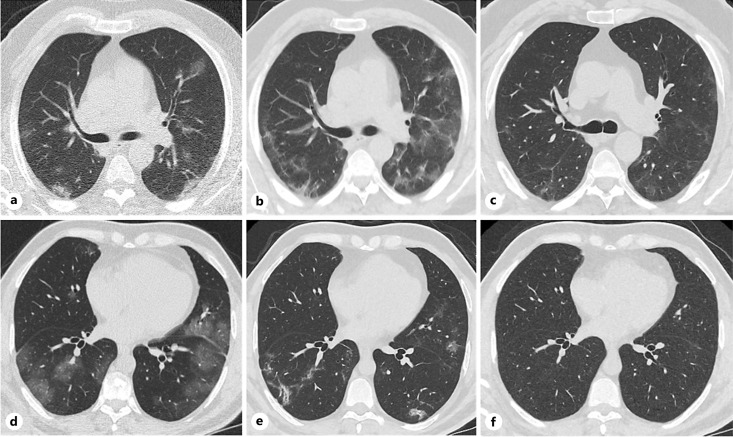

Results: The study involved 80 patients enrolled from 9 clinical centers. The mean age was 55.8 ± 18.5 years, and 27 of them (33.8%) were female. The average time to discharge was 7.8 ± 4.0 days in aviptadil group and 10 ± 5.0 days in placebo (p = 0.049). Modified Borg scales were not statistically different on day 3 (p = 0.090), but significantly lower in the aviptadil group on day 7 (p = 0.033). The CT lung damage score was not different on day 1 for both groups (p = 0.962); improvement on day 28 was significantly greater in the aviptadil group (p = 0.028). The death rate was also lower in the aviptadil group (5.1%) when compared to the placebo (12.2%). There was no drop-out due to side effects.